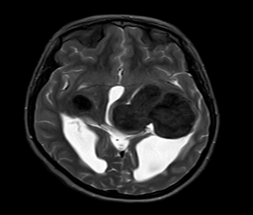

MRI outside hospital was done which was re-reported in our centre as Bilateral temporal lobe enhancing lesions. The left temporal lobe mass was larger in size and causing right-sided midline shift causing compression of the third ventricle with upstream hydrocephalus and transependymal seepage. These masses were reported as of neoplastic etiology, likely low-grade gliomas. Then MRI Brain with contrast was repeated which showed Bilateral intraventricular masses which are more or less stable in sizes causing hydrocephalus and compression effect at the level of the third ventricle towards the right side. Differentials included intraventricular tumors. No adjacent invasion is seen.

Figure 1: Lesion on T2 axial brain MRI.

The mean age of onset with nodal disease is 20.6 years with a male to female ratio of 1.4:1 [6,17]. Patients who develop intracranial involvement, however, become symptomatic at a mean age of 34.9 years, with a strong male preponderance. In intracranial RDD, the most involved structures are the suprasellar region, cerebral convexity, parasagittal region, cavernous sinus, and petroclival region [18,19]. Radiologically, the typical MRI findings include isointense to hypointense T1-weighted signals and hyperintense T2-weighted signals with homogeneous enhancement post-contrast. Bitemporal lesions often exhibit a dural-based, meningioma-like appearance [20]. Intracranial RDD is commonly confused with meningioma and requires tumor histopathology and immunohistochemistry for its definitive diagnosis.